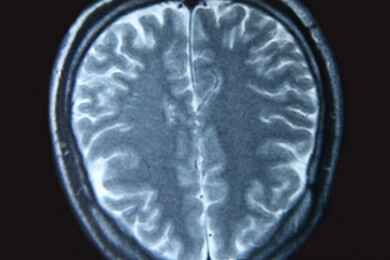

Ein Schlaganfall (Apoplex) ist eine plötzliche Unterbrechung der Gehirndurchblutung oder eine Blutung im Gehirn. Grund für einen Schlaganfall ist eine Hirn-Arteriosklerose (Thrombose), eine Hirn-Embolie oder Hirn-Blutung (hämorrhagischer Infarkt).